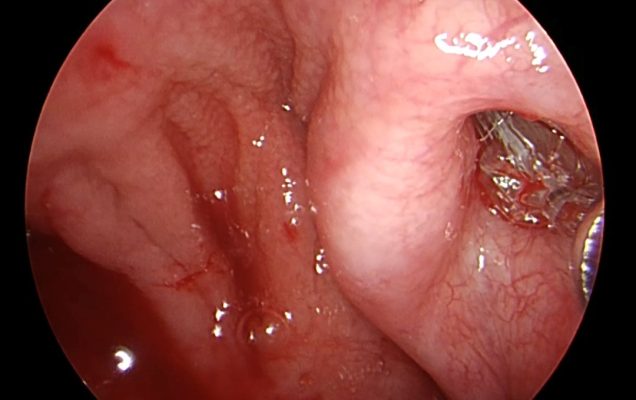

Balonikowanie trąbek słuchowych (trąbek Eustachiusza) to innowacyjna, małoinwazyjna metoda terapeutyczna stosowana u pacjentów z ich przewlekłą dysfunkcją. Schorzenie to może objawiać się uczuciem pełności w uszach, autofonią, pogorszeniem słuchu, nawracającymi infekcjami oraz trudnościami w wyrównywaniu ciśnienia – szczególnie odczuwalnymi podczas lotów samolotem czy nurkowania. Zabieg polega na wprowadzeniu przez jamę nosową cienkiego cewnika zakończonego balonikiem do ujścia gardłowego trąbki słuchowej, pod kontrolą endoskopową. Następnie balonik jest stopniowo wypełniany solą fizjologiczną, co pod działaniem ciśnienia około 10-12 atmosfer powoduje poszerzenie i przywrócenie drożności. Po krótkim czasie balon zostaje opróżniony i usunięty. Cała procedura wykonywana jest w znieczuleniu ogólnym i nie wymaga wykonywania widocznych nacięć.

Procedurę wykonała dr n. med. Marta Kwiatkowska, specjalizująca się m. in. w endoskopowej chirurgii ucha środkowego i zatok przynosowych.